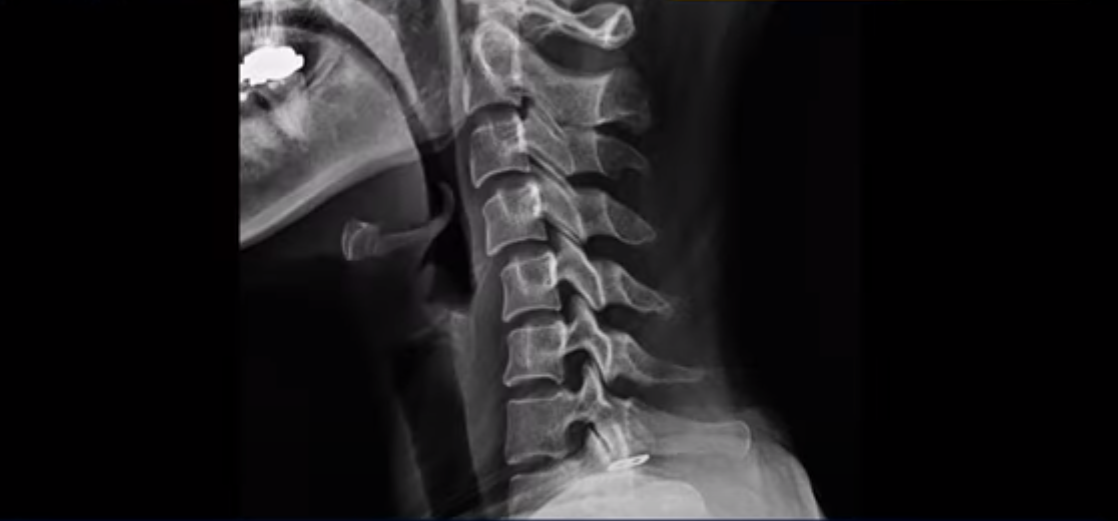

이분 X-ray에서 보시다시피 일자목 정도가 아니라 역 c자 형태의 목입니다.

이런 목 형태를 가지면 목이 안 아플 수가 없습니다. 그리고 목에 엄청난 부담을 주기 때문에 디스크가 퇴행되면서 찢어질 가능성이 높아지죠. 이 환자분은 오른쪽과 왼쪽이 모두 저리고 아픕니다. MRI를 보면 5번 6번 디스크가 오른쪽 파열되어 아래로 흘러내려가 있습니다.

더 윗마디 3번 4번을 보면 왼쪽으로 디스크가 밀려나가 있습니다.

이 환자분도 아까 X-ray에서 보여드렸듯이 아주 심한 일자목, 거북목이 있고 그 결과로 목의 거의 모든 마디가 다 퇴행이 진행되어 있죠. 즉 거북목은 모든 목질환, 특히 목디스크, 목협착증의 어머니 질환이며 그래서 목디스크를 치료하기 위해서는 반드시 거북목 때문에 짧아지고 뭉치고 굳고 뒤틀린 목 주변 근육들을 잘 치료해줘야 합니다.